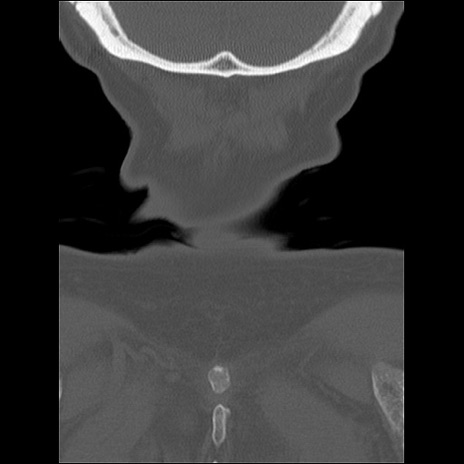

症例48 頚椎CT(冠状断像)

頚椎CT